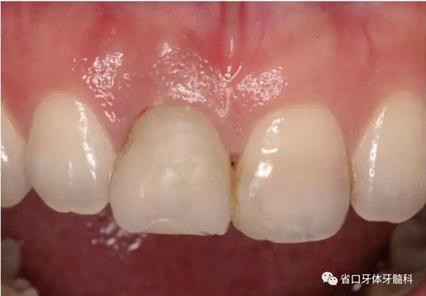

圖1 術(shù)前口內(nèi)照

圖2 術(shù)前口內(nèi)照

圖3 術(shù)前口內(nèi)照